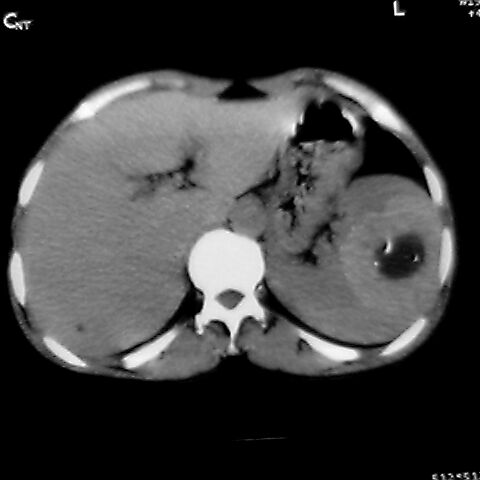

女 48岁 食道癌术前体检发现脾占位。

脾胀内部巨大低密度肿块,边界清或不清,中心坏死,轻度增强,内见散在钙化,结合食道癌病史多考虑:转移癌.

转移瘤不可能单发,考虑脾血管瘤。

1,脾血管瘤。2,右肝,右肾小囊肿。